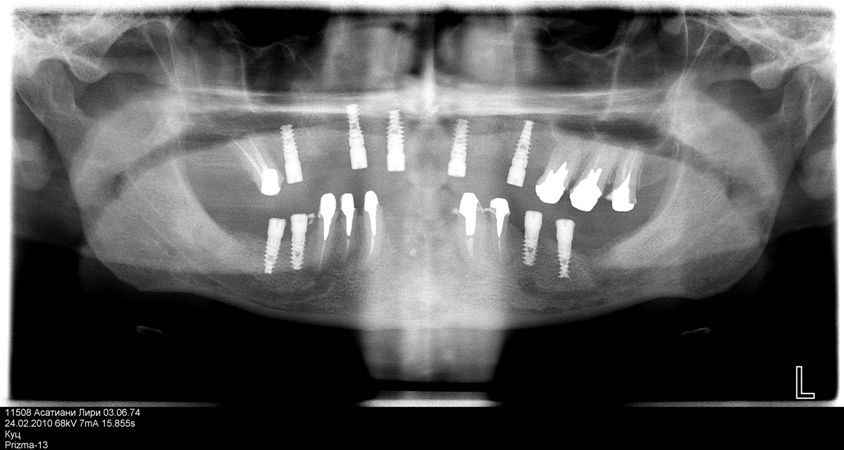

Removal of 15, 23, 31, 32, 38, 41, 42, 48 teeth and curettage of alveolar sockets were performed under infiltration anesthesia. The mucous membrane was cut along the alveolar crest in the area of 16, 14, 12, 22, 25, 36, 37, 46 and 47 teeth. Exfoliation of periosteal mucosal graft. Formation of bone bed. Placement of Alpha Dent Implants in the area of 12, 14, 16, 22, 25, 36, 37, 46 and 47 teeth (Photo 5). The implants are covered with screw-type plug. Suture of mucous membrane. Adjustment of temporary removable dental prosthesis. Administrations: antibiotic therapy, removal of stitches in seven days.